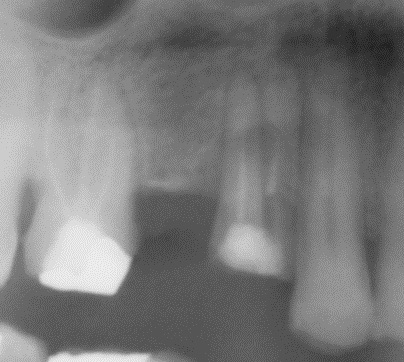

Preop: Racine de 14 fracturée par bridge.

La lyse osseuse n'intéresse uniquement que la partie palatine et l'ancienne zone de furcation de cette prémo.

La corticale vestibulaire est conservée et c'est elle même qui va servir de toile de tente pour conserver l'espace cicatriciel et garder un max d'os.